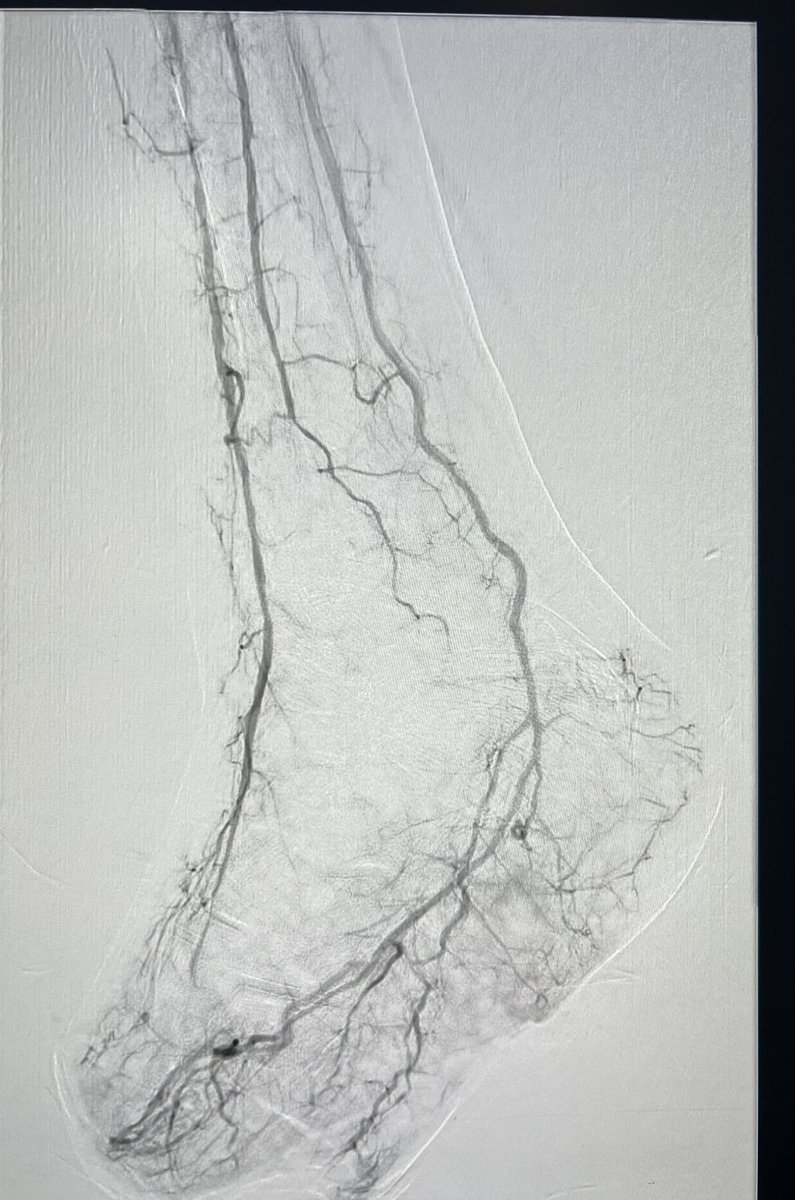

#CLTI in young diabetic patient ( 42y/o) , Rutherford class 5. Occluded PTA at the foot. Successful #Revascularization through #pedal loop technique. #limb_salvage #amputation_prevention #IR #endovascular #interventional

banderaldhafery's tweet image. #CLTI in young diabetic patient ( 42y/o) , Rutherford class 5.

Occluded PTA at the foot.

Successful #Revascularization through #pedal loop technique.